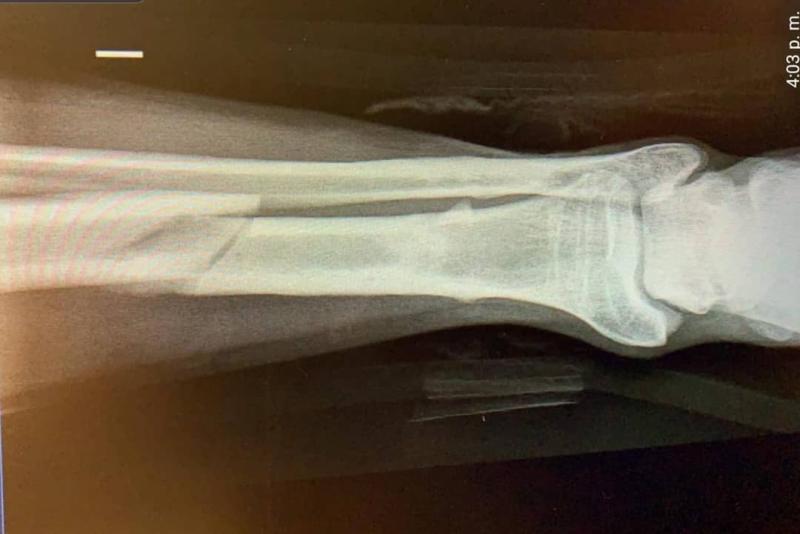

Fue un accidente que lo dejó en reposo y alejado de sus actividades normales. Durante fiestas patrias, Matías Assler, quien interpreta a Rafael en “Amor a la Catalán”, se cayó de un caballo, lo cual provocó que se fracturara la tibia.

Hay que recordar que el incidente que sufrió Assler se difundió luego de que su pareja, la actriz Juanita Ringeling, subiera una foto con él en camilla el pasado 23 de septiembre. “En las buenas y en las no tan buenas. Así está la cosa por acá”, escribió.